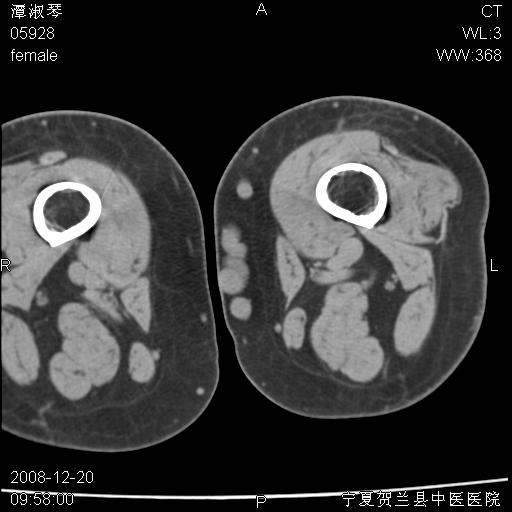

标题: CT17526:请各位看看是啥?

支持骨梗死,退行性骨关节病,膝关节积液.

考虑骨梗死可能性大

骨梗死可能性大

左股骨下段骨梗死。双膝退变。

左胫骨下端松质骨及髓腔内可见点片状高密度灶,骨皮质无明显膨胀及变薄。病变范围较长。支持骨梗死,退行性骨关节病,膝关节积液